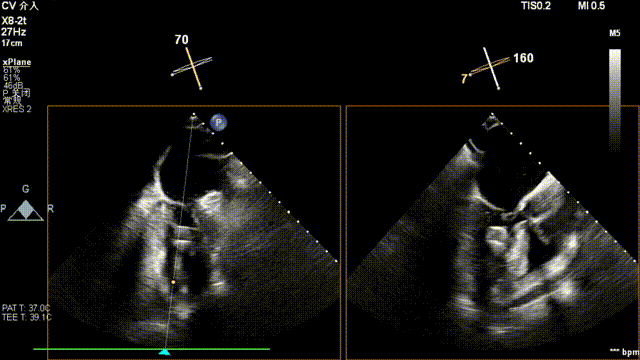

术后超声

最终在A3P2位置夹合,前叶夹合量10mm,后叶夹合量8mm,剩余瓣口面积3.45cm²,平均跨瓣压差2mmHg,反流基本消除。